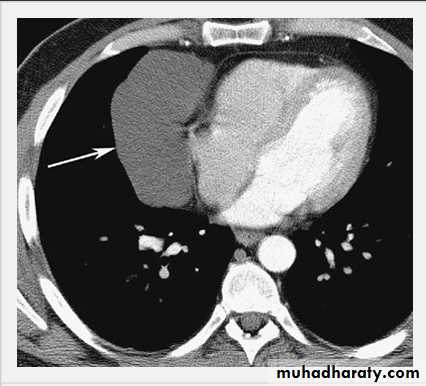

Empyema on Chest Radiograph and CT.

A. Posteroanterior chest film in a patient with a recent right lower pneumonia demonstrates an oval opacity in the right lateral costophrenic sulcus containing gas (arrow).

B. An enhanced CT scan shows a circumferential pleural fluid collection with enhancing visceral (straight arrow) and parietal (curved arrow) pleural layers representing an empyema.

Note the contained gas pockets, indicating loculations within the collection itself.